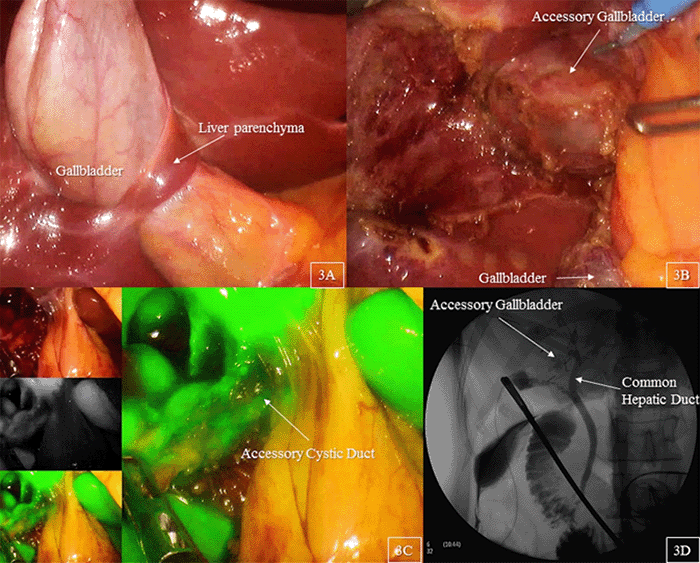

Figure 2. Magnetic Resonance Cholangiopancreatography Demonstrated an Oblong, Saccular Gallbladder with a Stone-Containing Accessory Gallbladder. Published with Permission

Her white blood cell count and liver function tests were within normal limits. Further workup showed gastritis on upper endoscopy. Her initial abdominal ultrasound from an outside facility did not detect any gallbladder anomalies but described choledocholithiasis within the right intrahepatic biliary duct with associated duct dilatation (Figure 1). These findings were subsequently confirmed with endoscopic retrograde cholangiopancreatography (ERCP); however, the stones were not retrieved out of concern for perforation and presumed need for surgical management. Following ERCP, the patient underwent magnetic resonance cholangiopancreatography (MRCP), which demonstrated an oblong, saccular gallbladder with a stone-containing accessory gallbladder or single dilated intrahepatic duct along the inferior inferomedial aspect of the right hepatic lobe, which was seen to communicate with the right hepatic duct (Figure 2).

Figure 3. Intraoperative Findings. Published with Permission

A) Showing superior portion of gallbladder body was circumferentially wrapped by thin tongue of liver parenchyma; B) accessory gallbladder was embedded in hepatic lobe; C) indocyanine green fluorescence was used to confirm anatomical variant of biliary structures; D); and intraoperative cholangiography demonstrated contrast filling stone-containing accessory gallbladder through accessory duct which came off from right hepatic duct

The patient underwent the operation with no intraoperative complications (Figure 3). Final pathology showed no histopathologic abnormality in both actual and accessory gallbladders. The accessory gallbladder was full of black-tan multifaceted calculi ranging from 0.1 to 0.3 cm in dimension; no stones were found in the native gallbladder. The postoperative course was uneventful, and the patient was doing well at a two-week follow-up.